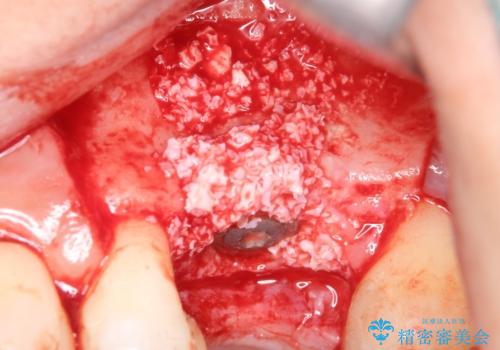

- 検査の結果、長くもたせることが困難な歯が確認された患者様です。

抜歯を行い、周囲の骨を増やしつつインプラントを埋入することとなりました。

良い位置に良い方向でインプラントを埋入することができました。